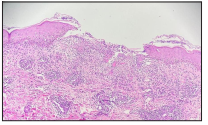

Figure1a Few deep erosions present over labiamajora, labia minora and vaginal mucosa.Figure 1b Multiple grouped vesicles, papulesand pustules present over nape of neck, chest,bilateral axilla, abdomen, back and rightleg. There were longitudinal ridges presentover nails of right foot. Ophthalmologic alexamination showed few erosions over left (3.4 mg/dl), and albumin to globulin ratio(0.89) was decreased. Rest of the investigations includingC reactive protein, electrolytes, liverfunction test, histogram, differential count,urea, creatinine and G6PD were normal. As per the clinical features, blood reports andhistopathological examination, patient waslabelled as case of Bechet’s diseasein HIV patient.